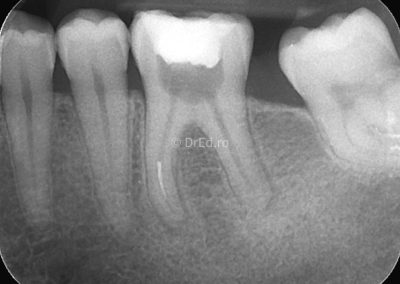

Galerie

Toate imaginile, fotografiile și radiografiile publicate pe acest site sunt protejate prin drepturi de autor și constituie proprietatea exclusivă a Dred.ro.

Aceste materiale sunt furnizate exclusiv în scop informativ și educațional și nu conțin date cu caracter personal sau informații care permit identificarea pacienților, în concordanță cu legislația privind protecția datelor cu caracter personal și GDPR.

Reproducerea, copierea, distribuirea, publicarea, transmiterea, modificarea sau orice altă utilizare, integrală ori parțială, a acestor materiale, în orice formă și prin orice mijloace, fără consimțământul prealabil scris al titularului drepturilor, este strict interzisă și poate atrage răspunderea civilă și/sau penală, în condițiile legii aplicabile privind drepturile de autor și protecția proprietății intelectuale.